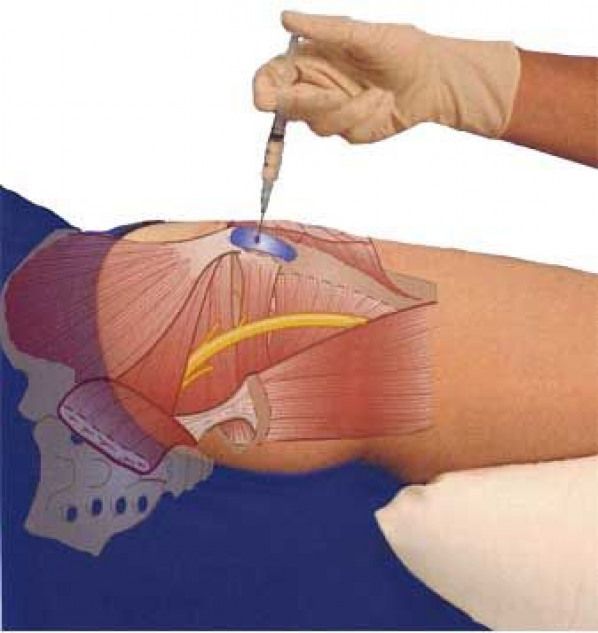

Здоровье суставов: Трохантерит и его влияние на мышцы